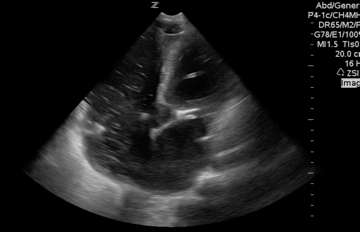

#POCUS and CPR: First Do No Harm, share your cases & tips for cardiac standstill & rhythm #foamed #foamus